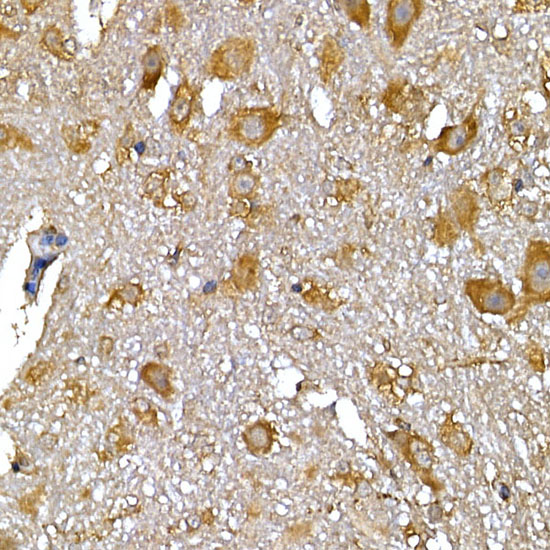

Immunohistochemistry analysis of paraffin-embedded Rat brain tissue using IRS-1 Antibody.